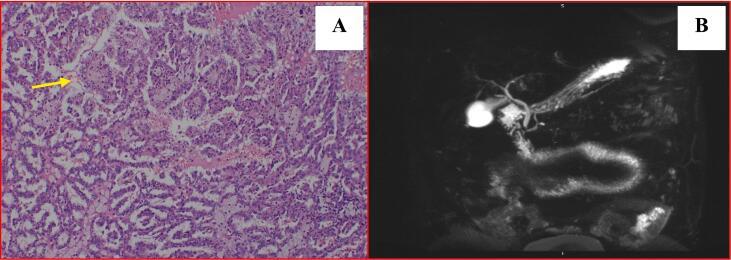

Stauffer's syndrome is a rare paraneoplastic non metastatic hepatic dysfunction related to renal cell carcinoma. It is characterized by elevated alkaline phosphatase, erythrocyte sedimentation rate, a-2-globulin, y-glutamyl transferase, thrombocytosis, prolongation of prothrombin time and hepatosplenomegaly, in the absence of hepatic metastasis. A rare variant of it with cholestatic jaundice is described in four cases so far in literature.

We present a case of a patient presented with features of cholestatic jaundice who was found to have a left sided renal cell carcinoma in the work up.

施陶费尔综合征是一种与肾细胞癌相关的罕见副肿瘤性非转移性肝功能障碍。其特征为碱性磷酸酶、红细胞沉降率、α-2球蛋白、γ-谷氨酰转移酶升高,血小板增多,凝血酶原时间延长以及肝脾肿大,且无肝转移。文献中迄今为止仅报道了4例伴有胆汁淤积性黄疸的罕见变异型病例。

我们报告1例表现为胆汁淤积性黄疸的患者,在检查过程中发现患有左侧肾细胞癌。